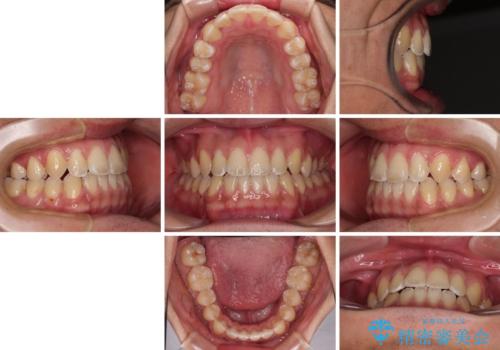

- 前歯のデコボコを気にして来院された患者様です。

歯列としてはワイヤー装置でもインビザラインでも対応可能でしたが、インビザラインが苦手とする上顎側切歯(真ん中から2番目の歯)の舌側転位が顕著でした。

治療の確実性を上げるために、インビザライン開始前に上顎のワイヤー装置にて舌側転位を解消し、その後インビザラインにて矯正治療を行うこととしました。

前歯のデコボコが早めに改善され、スムーズに治療を終えることができました。